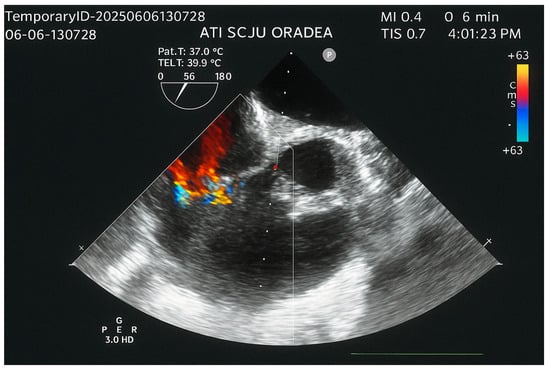

Swinging Mass Through the Pulmonary Valve: A Rare Case of Right Ventricular Myxoma

Primary cardiac tumors are rare, with an estimated incidence of 0.001% to 0.3% in autopsy series. Most are benign, the most common being cardiac myxomas, which typically originate in the left atrium. Right ventricular myxoma is among the rarest primary cardiac tumors, and its true incidence is difficult to determine, as most data come from isolated case reports. This paper aims to report a case of right ventricular myxoma in a young woman with a history of childhood malignancy and to discuss the possible association between the two conditions. Echocardiography, thoracic computed tomography (CT), and pulmonary CT angiography were used to assess the presence, location, and size of the tumor. The definitive diagnosis was established by histopathological examination. A 34-year-old woman, with a past medical history of acute lymphoblastic leukemia (ALL) in childhood, presented with a dry cough and exertional dyspnea persisting for three weeks. Transthoracic echocardiography revealed a mass located in the right ventricular outflow tract (RVOT), attached near the tricuspid valve and intermittently prolapsing into the pulmonary trunk. CT imaging confirmed the presence of the tumor in the RVOT and the main pulmonary artery. Because of the high risk of massive pulmonary embolism, the patient underwent urgent surgical excision of the tumor. Histopathological analysis confirmed the diagnosis of cardiac myxoma. The postoperative recovery was uneventful, and the three-month follow-up showed no recurrence or signs of pulmonary embolism. The patient’s history of ALL raised the question of a possible association; however, a review of the literature revealed no previously reported link. In conclusion, right ventricular myxomas are extremely rare. The occurrence of cardiac myxoma in this patient following childhood ALL appears to be incidental. Further research is needed to determine whether ALL survivors have an increased predisposition to subsequent cardiac tumors. Full article

Show Figures

Figure 1